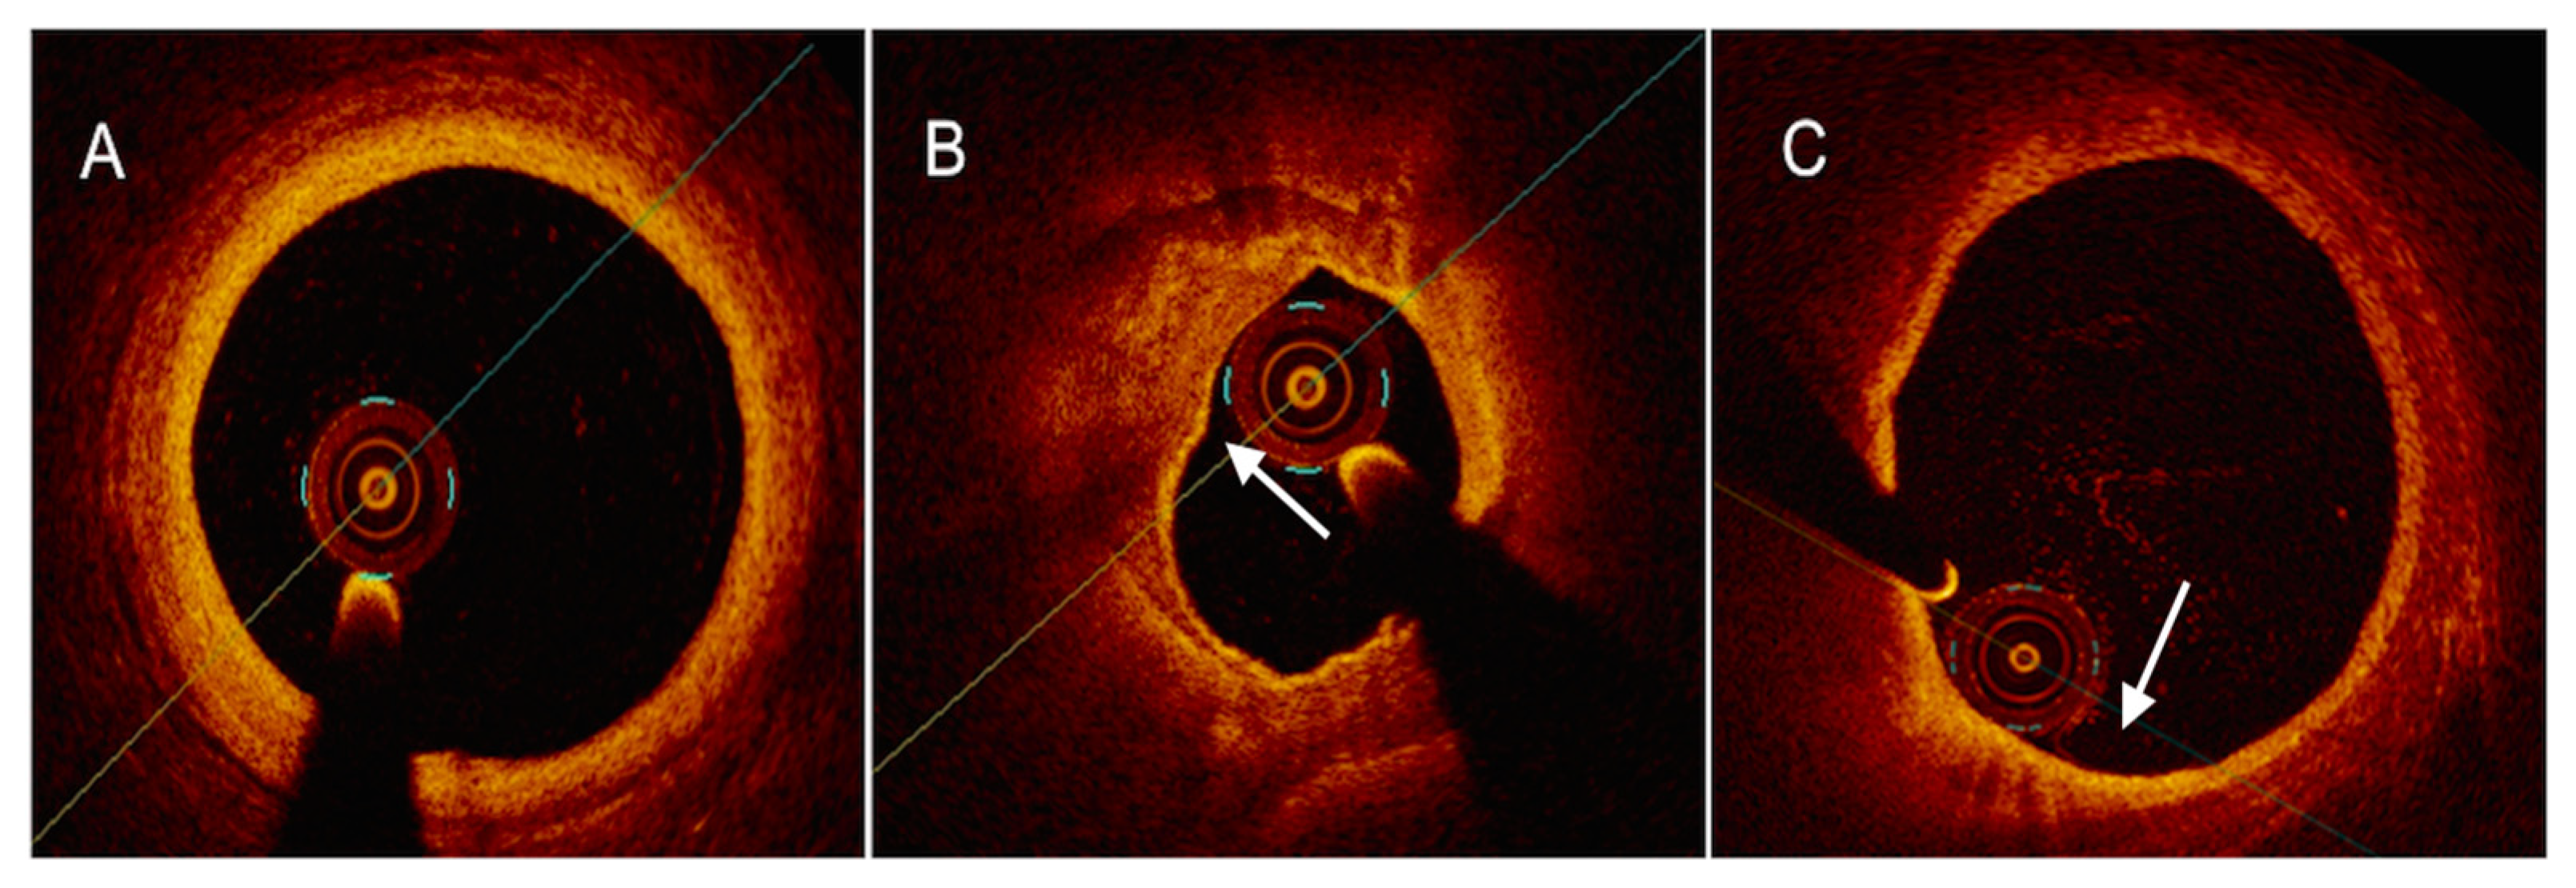

4.2. Optical Coherence Tomography

4.3. Near-Infrared Reflectance Spectroscopy